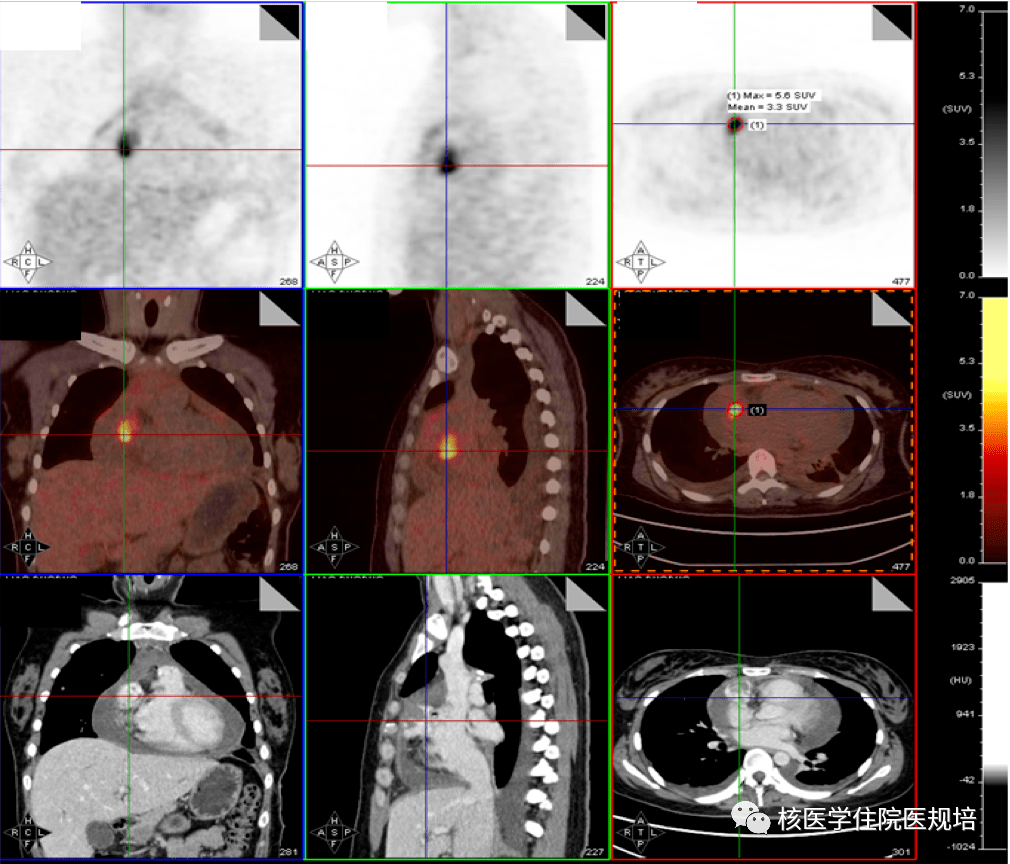

规培朋友看过来--核医学病例及解析(183号)

1010x864 - 275KB - PNG

规培朋友看过来--核医学病例及解析(183号)

531x635 - 130KB - PNG